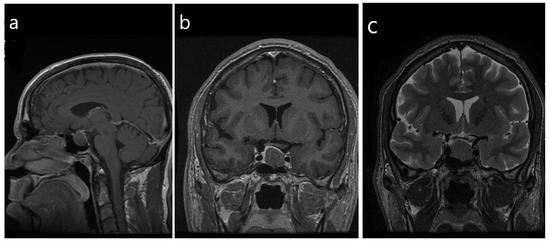

- Heck, A.; Ringstad, G.; Fougner, S.L.; Casar-Borota, O.; Nome, T.; Ramm-Pettersen, J.; Bollerslev, J. Intensity of pituitary adenoma on T2-weighted magnetic resonance imaging predicts the response to octreotide treatment in newly diagnosed acromegaly. Clin. Endocrinol. 2012, 77, 72–78. [Google Scholar] [CrossRef]

- Heck, A.; Emblem, K.E.; Casar-Borota, O.; Bollerslev, J.; Ringstad, G. Quantitative analyses of T2-weighted MRI as a potential marker for response to somatostatin analogs in newly diagnosed acromegaly. Endocrine 2016, 52, 333–343. [Google Scholar] [CrossRef] [PubMed]

- Potorac, I.; Petrossians, P.; Daly, A.F.; Alexopoulou, O.; Borot, S.; Sahnoun-Fathallah, M.; Castinetti, F.; Devuyst, F.; Jaffrain-Rea, M.L.; Briet, C.; et al. T2-weighted MRI signal predicts hormone and tumor responses to somatostatin analogs in acromegaly. Endocr. Relat. Cancer 2016, 23, 871–881. [Google Scholar] [CrossRef] [PubMed]